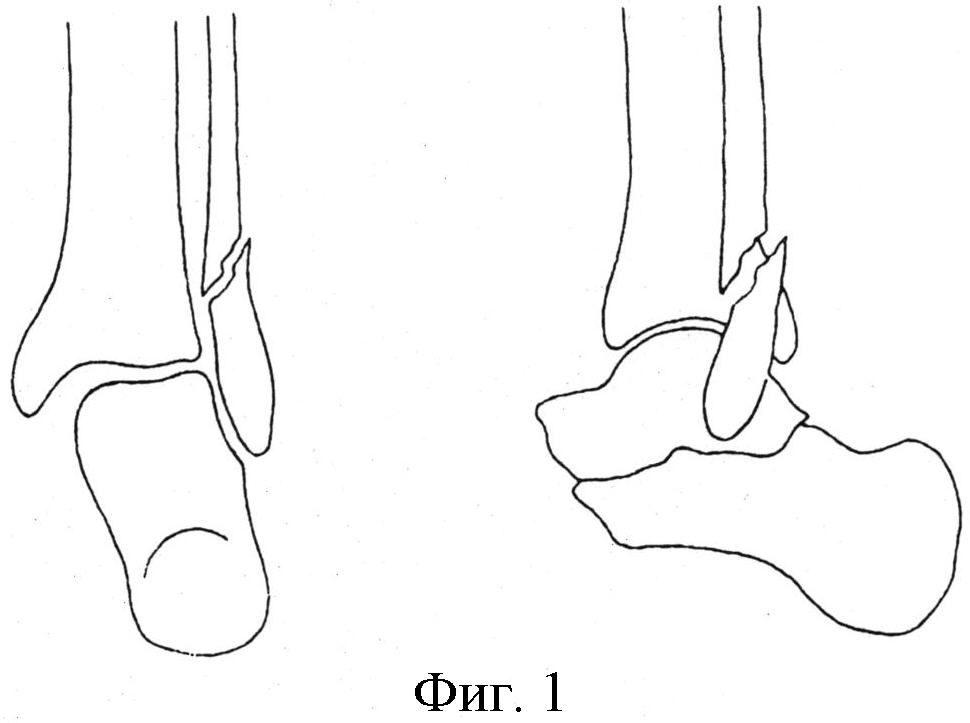

на фиг.4 - вид голени с установленным аппаратом внешней фиксации;

Пациент Т., 1967 г.р., ист./б. №902, находился на лечении в отделении травматологии с 28.02. по 09.03.2009 г. с диагнозом: закрытый перелом наружной лодыжки, повреждение дельтовидной связки, дистального межберцового синдесмоза справа, подвывих стопы кнаружи. На рентгенограмме (фиг.3) имеет место перелом наружной лодыжки со смещением, повреждение дистального межберцового синдесмоза, подвывих стопы кнаружи. Операция: закрытый ЧКОС перелома дистального суставного отдела костей голени аппаратом внешней фиксации 04.03.2009 г. В нижнюю треть и дистальный метафиз большеберцовой кости и пяточную кость введены костные стержни Шанца, закреплены на кронштейнах кольцевой и дуговой опор аппарата внешней фиксации, в дистальный отломок наружной лодыжки введен аналогичный стержень, закреплен на кронштейне, установленном на кольцевой опоре аппарата (фиг.4). Аппарат демонтирован, снят 28.04.2009 г. Курс восстановительного лечения в стационаре. Контрольный осмотр 04.10.2010 г., 16.10.2012 г. Пациент жалоб не предъявляет. Трудоспособность восстановлена. Нагрузка на стопу полная. Движения в голеностопном суставе в полном объеме. Исход лечения оценен как отличный (фиг.5).